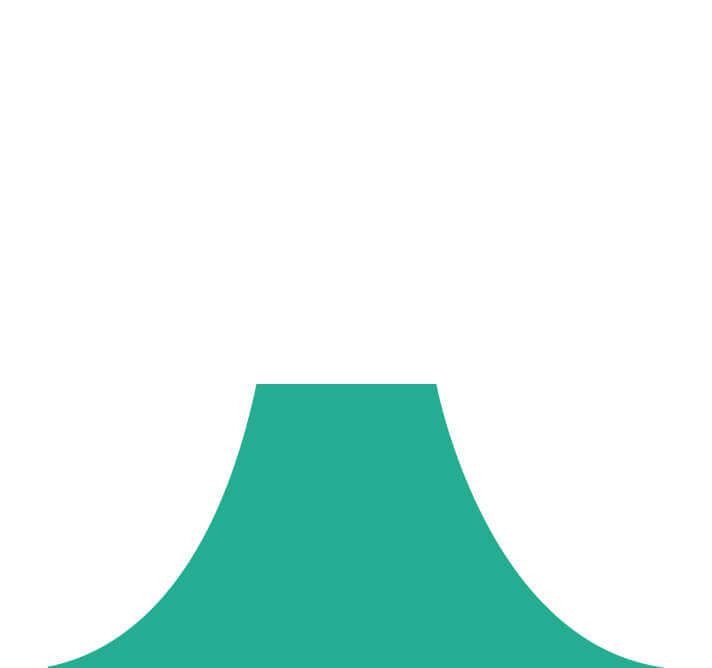

(Spectral Focused lmaging, SFI)

能够凸显黏膜浅层和中层血管轮廓,适用于中、远景观察下的病灶识别和早癌筛查。

照明光谱

照明光谱

光谱提取

光谱提取

光谱提取能量汇聚

光谱提取能量汇聚

RGB图像重建

RGB图像重建

染色模式显示

染色模式显示